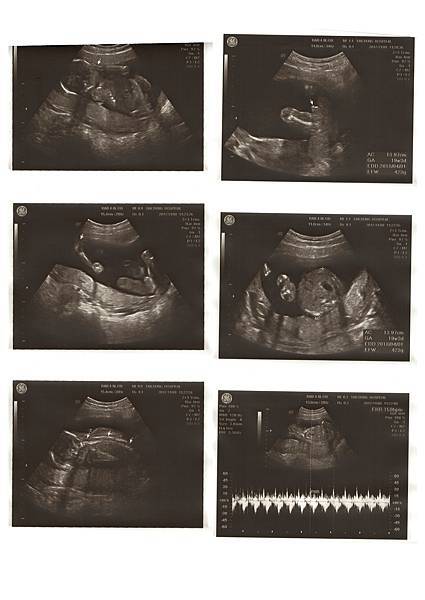

19W5D 產檢日,這次有量到寶寶的體重了!515g,醫生照了一些地方,都說在標準值,在照的時候寶寶的腿一直踢,Chris說寶寶的大腿感覺很有肉,好可愛呀。